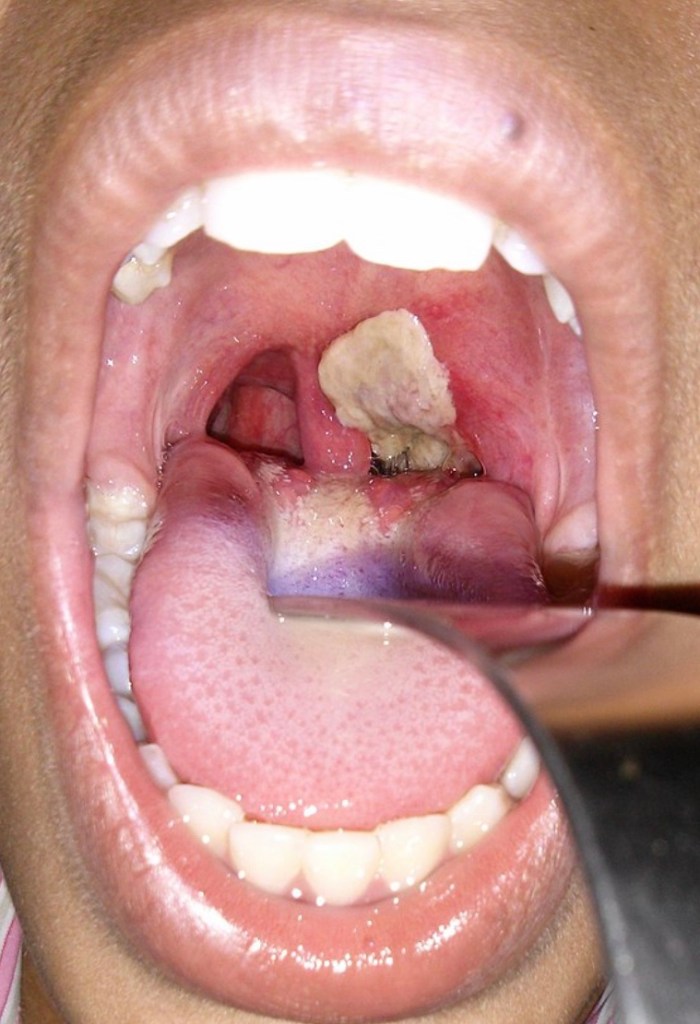

4. Diphtheria is a respiratory tract infection that cause severe pharyngitis with a thick membrane over the throat. This can be dangerous if left untreated. Prompt antibiotic therapy will be needed.